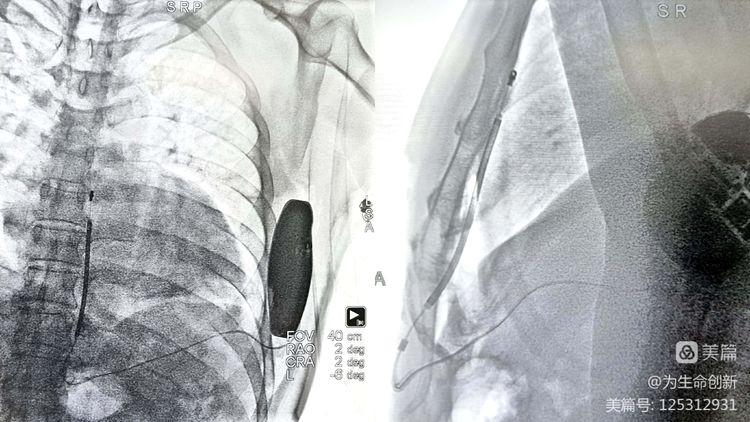

手术由心律失常中心资深术者刘可医生主刀,在心律失常中心团队默契配合下,从消毒、铺巾、局麻——根据标记位置做剑突旁切口、脉冲发生器囊袋——隧道针打隧

道过电极及固定电极——连接脉冲发生器,缝合伤口等每一个步骤都尽善尽美,术视野清晰,术程顺利,安返病房

术后影像:电极贴靠良好